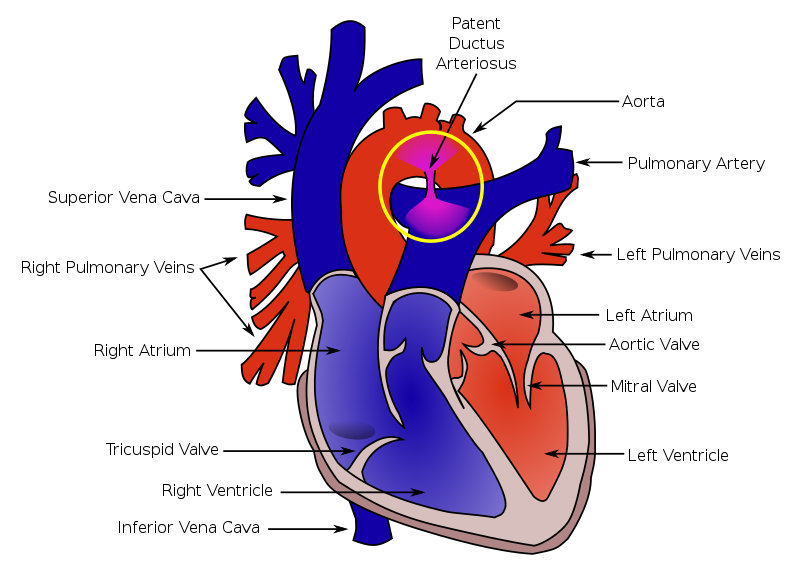

Patent Ductus Arteriosus (PDA)

A patent ductus arteriosus (PDA) results from failure of the ductus arteriosus close.

Patent ductus arteriosus (PDA) is linked to congenital rubella.

Patent ductus arteriosus (PDA) results in a left-to-right shunt between the pulmonary artery and the aorta.

The ductus arteriosus generally diverts blood away from the lungs and toward the aorta during development.

Patent ductus arteriosus (PDA) is typically asymptomatic at birth with a holosystolic ‘machine-like’ murmur.

Patent ductus arteriosus (PDA) may result in lower extremity cyanosis and Eisenmenger syndrome.

Treatment of patent ductus arteriosus (PDA) involves indomethacin, which decreases prostaglandin E1 (PGE1), resulting in PDA closure.

Note that PGE1 maintains patency of the ductus arteriosus.